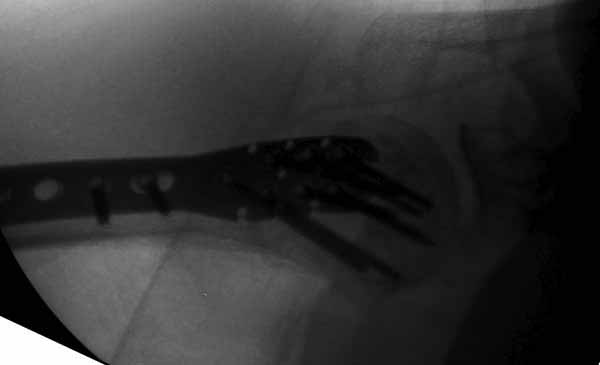

Уважаемы коллеги! Прошу помочь определиться с тактикой лечения пациентки. В феврале в отделение поступила пациентка с оскольчатым переломо-вывихом головки плечевой кости. Выполнена операция -остеосинтез блокируемой пластиной. Костная пластика не производилась. На контрольных рентгенограммах остается сублюксация головки и смещение большого бугорка. Интраоперационно бугорок подшивался с помощью лавсановых нитей. Послеоперационно: ношение косыночной повязки и пассивные движения в плечевом суставе в течение 2,5-х месяцев без особенностей. Через 2,5 месяца при попытке выполнения пассивно-активных движений произошел передний вывих плечевой кости.Вся реабилитация производилась по месту жительства. Таким образом существование вывиха в течение 1 месяца. Боли не беспокоят. Нейрососудистых нарушений в конечности нет. Что вы можете посоветовать: пластику, эндопротез, артродез? Заранее спасибо.

Здесь результат похожего случая, больная 87 лет, отягощенная сердечными делами и два года назад установка pacemaker и нескольких стентов. На третий день, сегодня утром сделали операцию. Послеоперационный псевдовывих связанный с релаксацией мышц и общим обезболиванием.